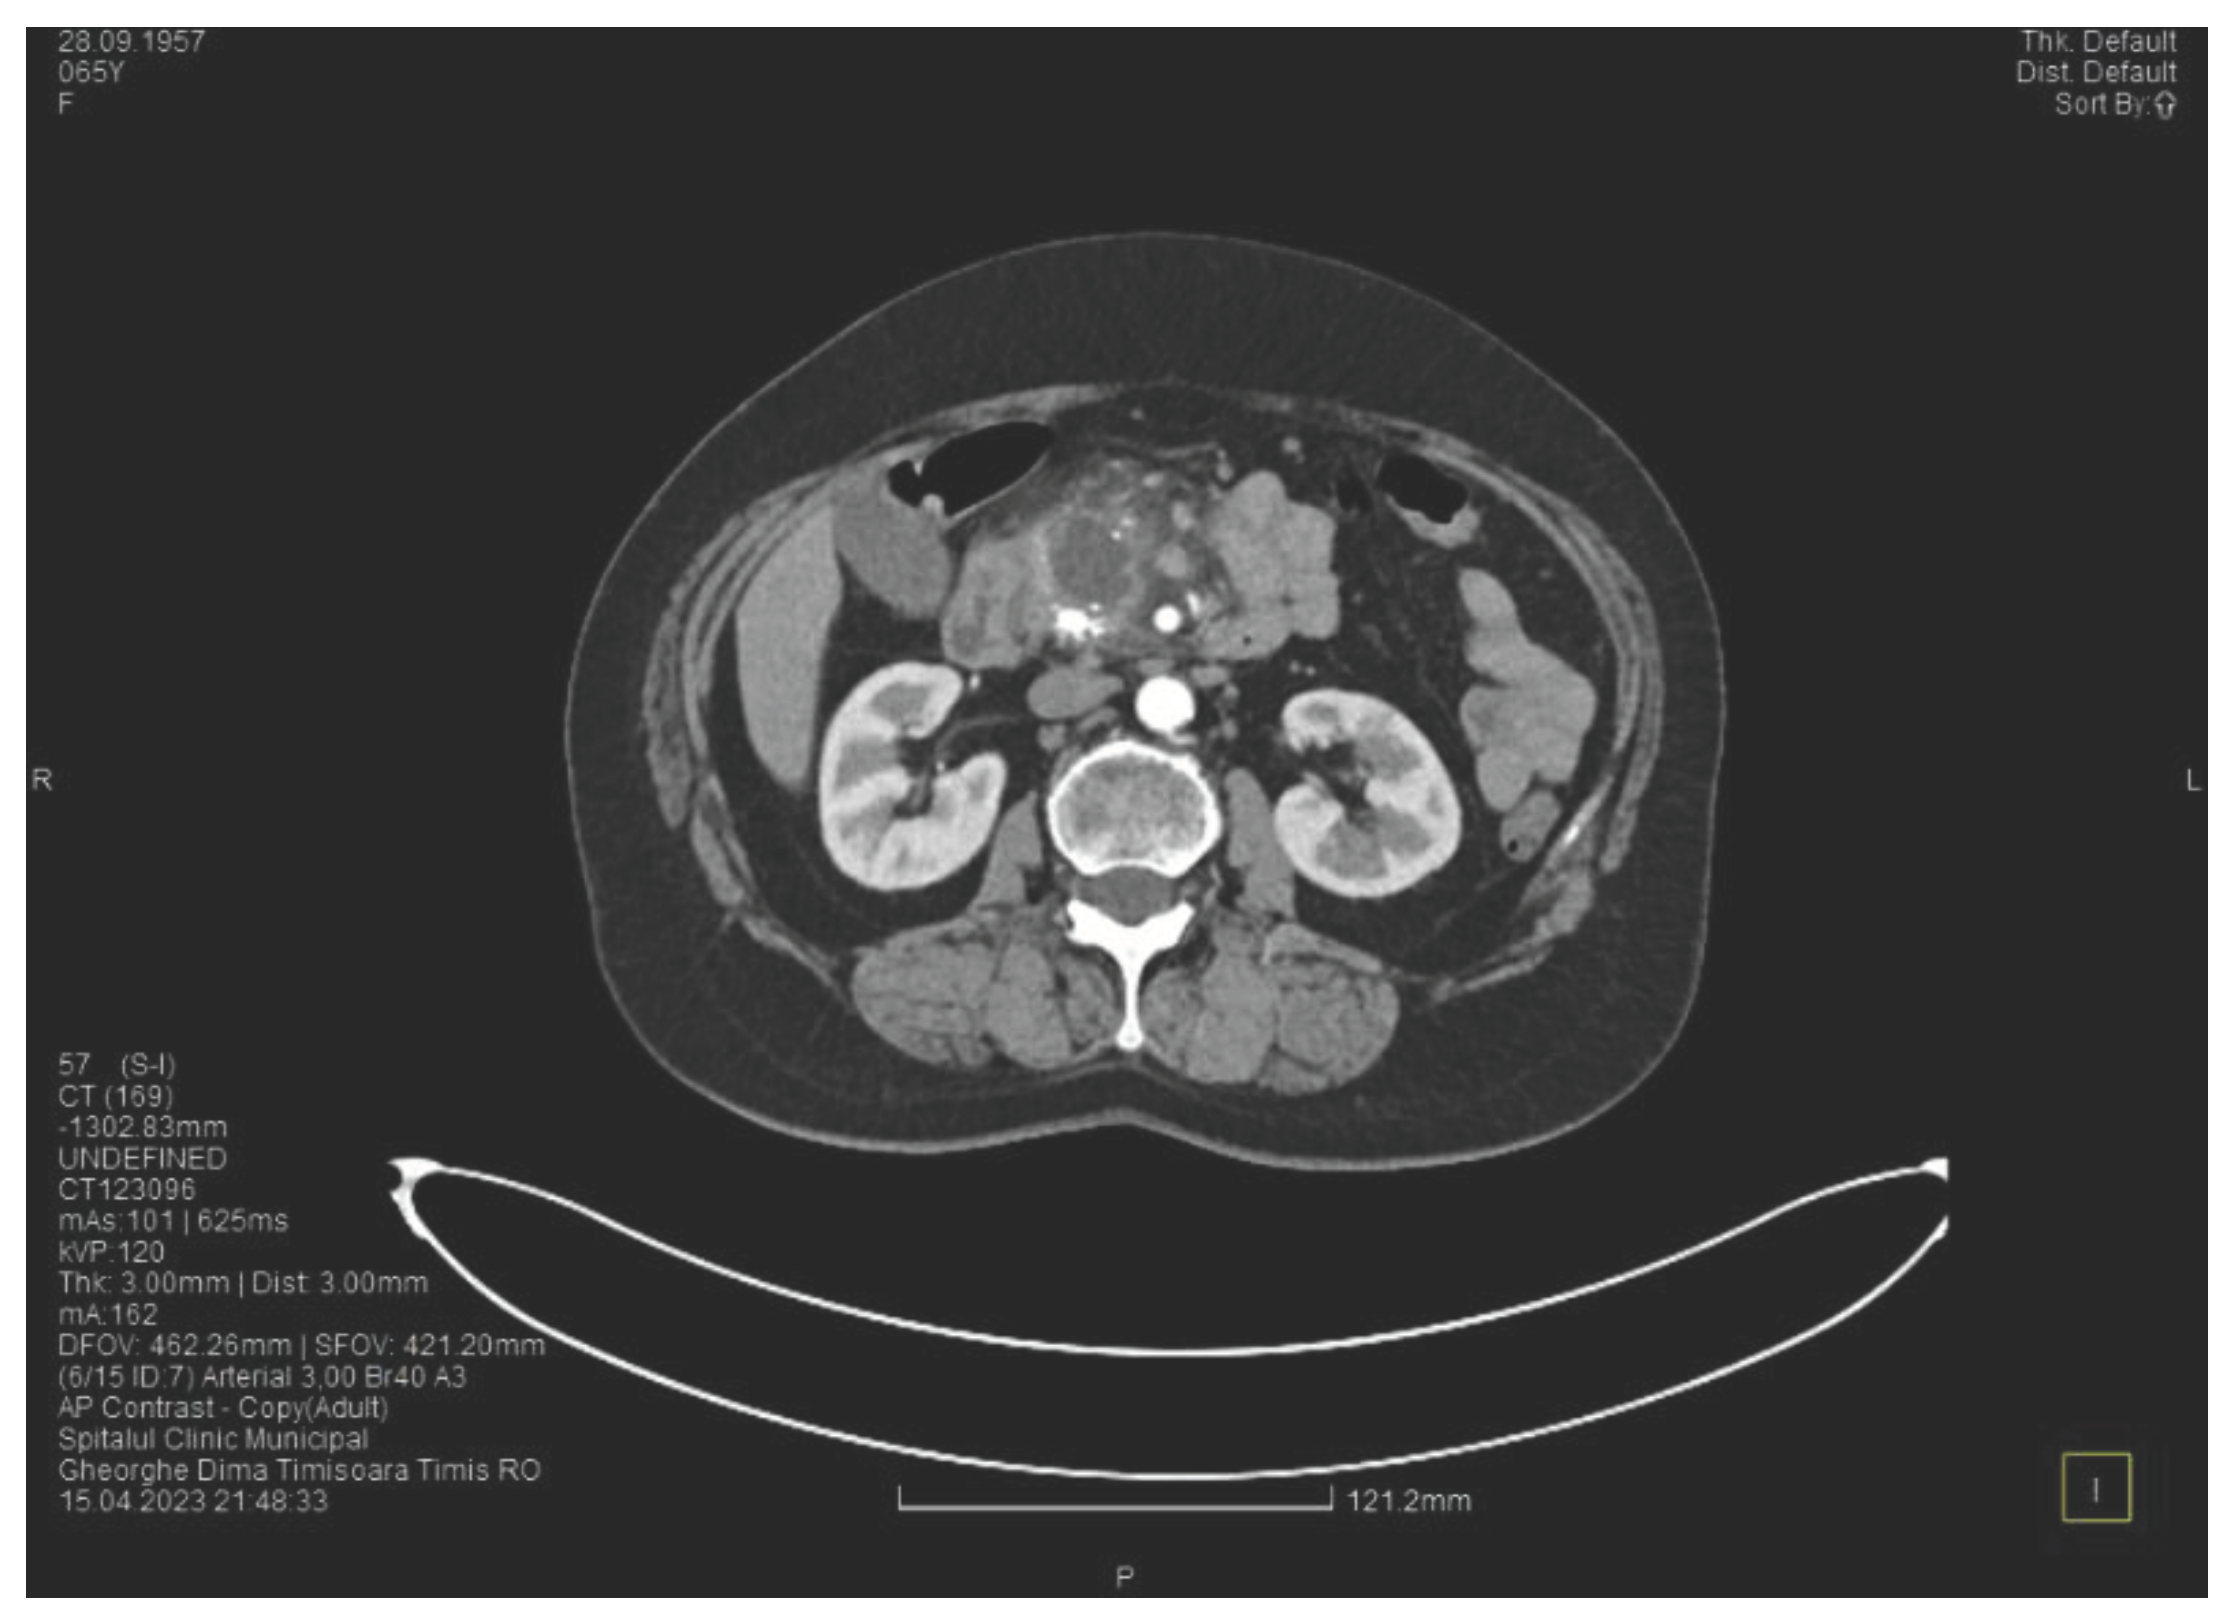

Contrast enhanced computed tomography highlighted signs of chronic pancreatitis with multiple calcifications throughout the pancreatic parenchyma, calcareous conglomerates in the cephalic area (Figure 6), dilatation of the Wirsung duct of approximately 15 mm, a cephalo-uncinate pseudocyst sized 30/31/32 mm (Figure 5), densification of the pericephalic pancreatic fat, all the changes being more pronounced compared to the previous examinations. Other findings were acute cholecystitis with thickening of the gallbladder wall and iodophilia of the mucosa, small dilatations of the intrahepatic bile ducts, fluid accumulation in the hepatic hilum and in the periduodenal area, inflammatory wall thickening in the gastric antro-pyloric region and in the duodenum (I, II), and inflammatory lymph nodes in the peripancreatic area and in the hepatic hilum with a size of up to 11 mm.

Figure 5. CT scan at the fourth episode of acute pancreatitis shows a slightly increased cyst and calcifications in the pancreatic head.

Figure 6. CT scan at the fourth episode of acute pancreatitis shows calcifications in the pancreatic head, thickening of the duodenal wall and the partial occlusion of the duodenum.